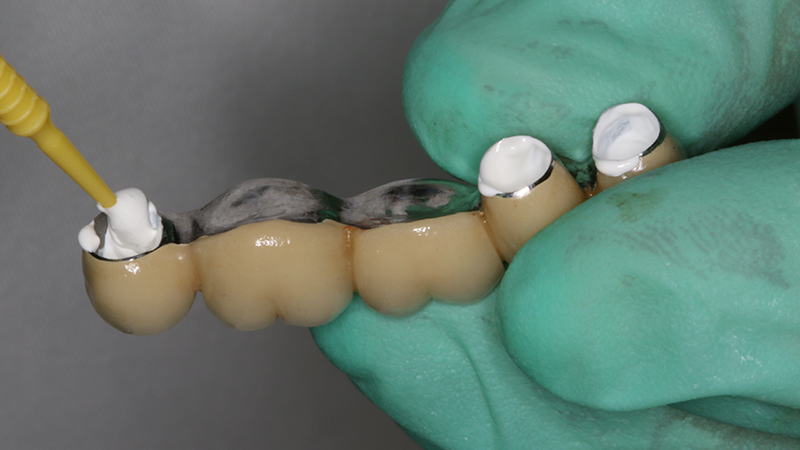

La finalizzazione del caso avveniva con protesi in metallo-ceramica passivata su cappe conometriche in bocca (Figs. 24, 25, 26, 27, 28, 29, 30, 31, 32) e radiografie finali ad un anno dal carico (Figs. 33, 34).

Applicazione ponte 17-14 in metallo ceramica su cappette conometriche passivate in bocca mediante cemento

Fig. 24 - Applicazione ponte in metallo ceramica su cappette conometriche passivate in bocca mediante cemento Multilink Hybrid e risultato finale

Applicazione ponte 17 - 14 in metallo ceramica su cappette conometriche passivate in bocca mediante cemento Multilink Hybrid e risultato finale

Fig. 25 - Applicazione ponte 17 - 14 in metallo ceramica su cappette conometriche passivate in bocca mediante cemento Multilink Hybrid e risultato finale